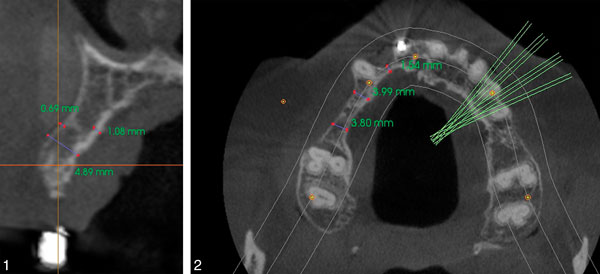

Diagnosis of alveolar bone should first be assessed visually for width and height and the relationships of teeth to one another and to the dental arch. Radiographic images can distinguish two-dimensional versus three-dimensional bone deficiency. A three-dimensional or volumetric bone evaluation with cone-beam computed tomography allows for precise measurement of the ridge and evaluation of both the cortical and medullary portion of the bone, which are imperative for the stability of the implant.